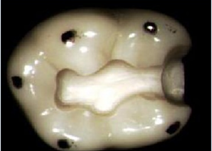

嵌體根據覆蓋牙面的不同,可以分為單面嵌體、雙面嵌體和多面嵌體,如圖所示:

(1)單面嵌體

(2)雙面嵌體

(3)多面嵌體